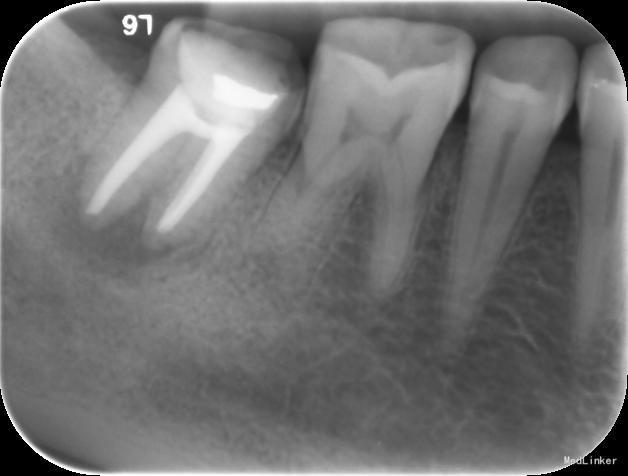

检查:右下7髓腔开放,可见髓腔内食物残渣及部分银汞充填体,叩痛(++), 冷热刺激无反应,松动1度,牙体已制备,牙合龈距离低,X线片示根尖区密度减低区。

诊断:难治性根尖周炎 治疗计划:告知患者病情,治疗难度及预后,拟行根管再治疗,但术后效果不确定,如若不理想拟需行根尖手术甚至牙拔除术。患者知情同意,并要求尽量行保留牙齿治疗。 处置:第一次 揭全髓顶,去腐,疏通根管,测量工作长度,机扩预备至S1,超声荡洗,激光消毒,封CP球。口服抗炎药。一周后复诊。 第二次 复诊无叩痛,暂封物在。去除暂封物,双氧水和盐水交替冲洗,EDTA伴随下根管预备至F2,超声荡洗,激光荡洗+激光消毒,封氢氧化钙。两周后复诊。 第三次 复诊无叩痛,暂封物在。 去除暂封物,双氧水和盐水交替冲洗,EDTA伴随下根管预备至40号,超声荡洗,激光荡洗+激光消毒,封vitapex,玻璃离子体充填。拍X线片。一月后复诊。 第四次 复诊无疼痛 旧充填体在 拍X线片可见根尖阴影变小,故未行任何治疗,嘱患者1月后再次复诊。 第五次 复诊无疼痛 旧充填体在 拍X线片未见根尖阴影变小,故去除旧充填体,冲洗,去除vitpex,根管再次预备,双氧水和盐水交替冲洗,超声荡洗,激光荡洗+激光消毒,封氢氧化钙。两周后复诊。 第六次 复诊无疼痛 去除暂封物,冲洗,见根管内无渗出,试尖,超声荡洗,激光荡洗和消毒,干燥,AHplus糊剂和热牙胶充填,糊剂超填,玻璃离子体充填。请口腔外科医生会诊是否可行根尖手术,外科医生建议因手术难度大,且病变与下颌神经管接近,建议随诊观察,暂不考虑行根尖手术。必要时考虑意向性牙再植术或者牙拔除术。嘱患者1月后复诊,结果患者失诊。